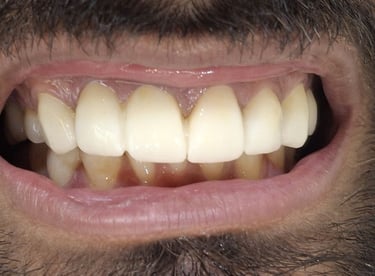

Before

After

All images shown here are real teeth cleaning cases treated at our clinic with patient consent.

Professional teeth cleaning helps remove plaque, tarter, and surface stains that regular at home brushing can not.

At Shree Dental Care, teeth cleaning is performed gently with focus on patient experience, comfort and long term oral health.